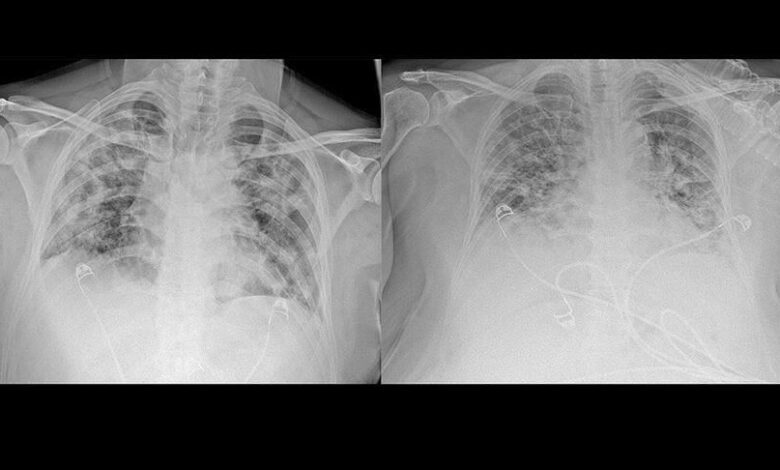

Koronavirus najviše oštećuje pluća, a tomografski snimci jasno pokazuju koliko infekcija COVID-19 oštećuje taj organ, javlja Anadolu Agency (AA).

Neki od glavnih simproma zaraze koronavirusom su zatajenje respiratornog trakta, otežano disanje i upala pluća, a o posljedicama koje pluća trpe od koronavirusa i brzini razvoja bolesti ponajbolje govore tomografski snimci pacijenata koje je AA dobila iz Gradske bolnice u Ankari.

Upozorivši da koronavirus oštećuje sve vitalne organe, Karalezli je kazala da je to najizraženije kod pluća, a to je pokazala i na tomografskim snimcima pluća pacijenata.

Ističući da postoje uočljive razlike između pluća zdrave osobe i pacijenta zaraženog koronavirusom, Karalezli je napravila takve snimke kako bi ljudima jasnije ukazala na posljedice infekcije COVID-19.